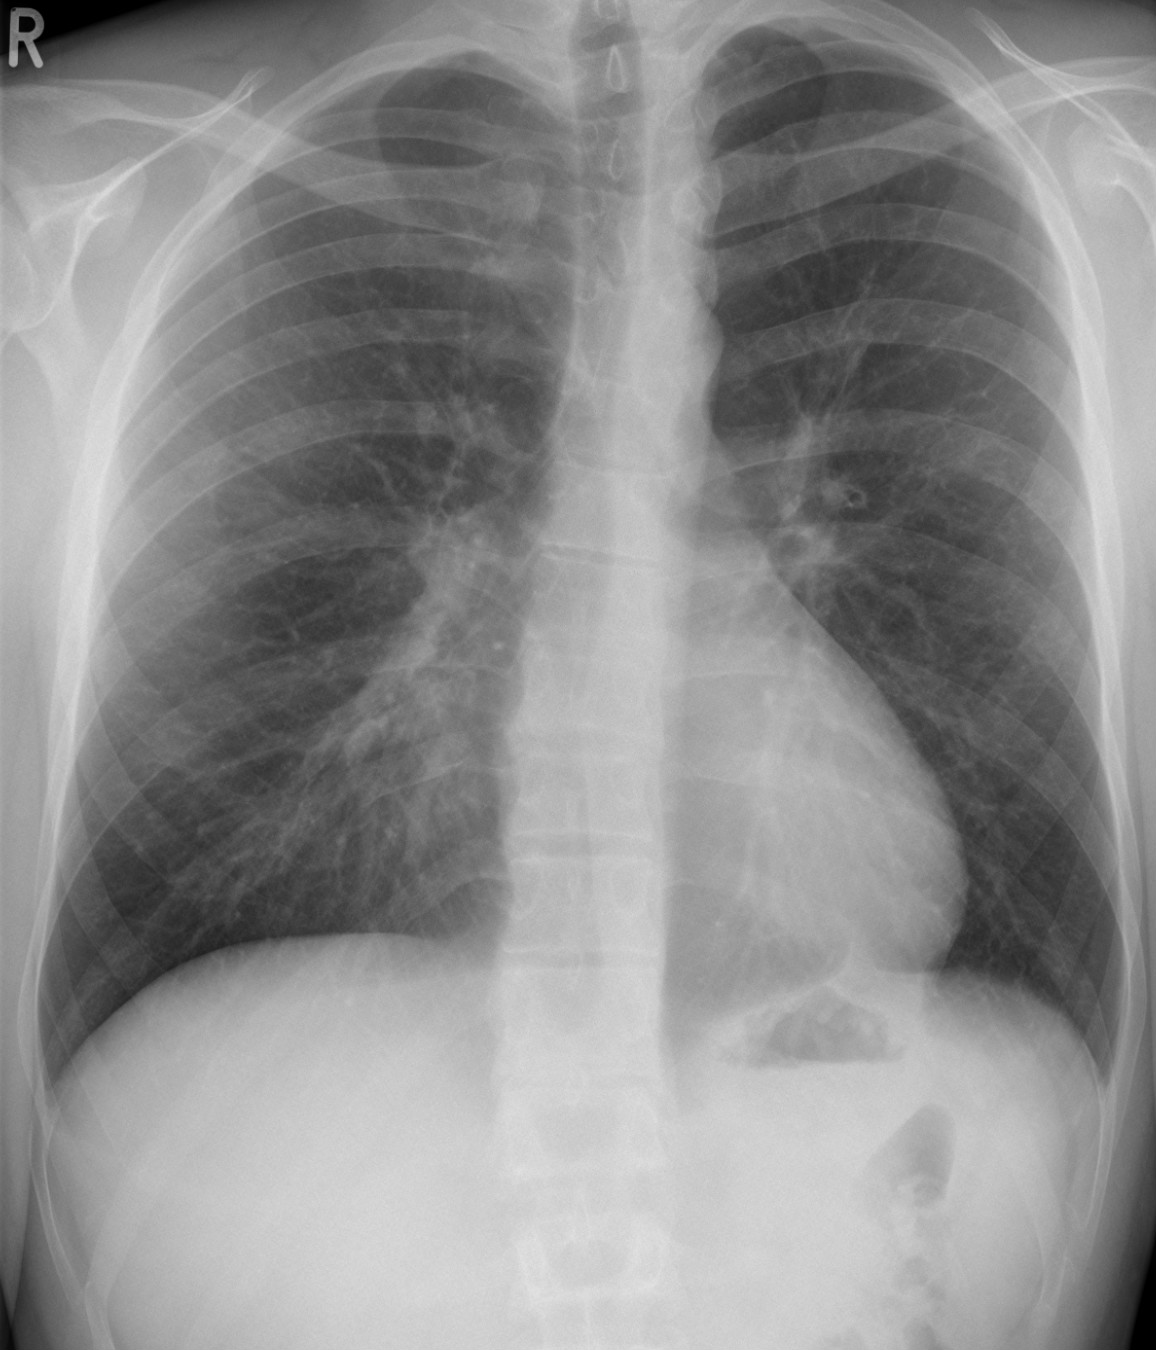

가슴 엑스레이도 진단에 유용하다. 오목가슴의 가슴 엑스레이는 오른쪽 폐 부위에 폐렴에서 보이는 것과 같은 침윤으로 오인될 수 있는 불투명성을 나타낼 수 있다.[18] 일부 연구에서는 기능에 제한이 없는 개인의 경우 CT 스캔 대신 가슴 엑스레이를 기반으로 Haller 지수를 계산할 수 있다고 제안한다.[19]

가슴 엑스레이도 진단에 도움이 된다. 오목가슴의 경우, 가슴 엑스레이에서 오른쪽 폐 부위에 폐렴과 혼동될 수 있는 불투명한 부분이 보일 수 있다.[18] 일부 연구에서는 기능 제한이 없는 사람의 경우 CT 스캔 대신 가슴 엑스레이를 통해 Haller 지수를 계산할 수 있다고 한다.[19]

가슴 엑스레이도 진단에 유용하다. 오목가슴의 가슴 엑스레이는 오른쪽 폐 부위에 침윤(예: 폐렴에서 보이는 것과 같은)으로 오인될 수 있는 불투명성을 나타낼 수 있다.[18] 일부 연구에서는 기능에 제한이 없는 개인의 경우 CT 스캔 대신 가슴 엑스레이를 기반으로 Haller 지수를 계산할 수 있다고 제안한다.[19]

가슴 엑스레이도 진단에 도움이 된다. 오목가슴의 가슴 엑스레이는 오른쪽 폐 부위에 폐렴에서 보이는 것과 같은 침윤으로 오인될 수 있는 불투명성을 나타낼 수 있다.[18] 일부 연구에서는 기능에 제한이 없는 사람의 경우 CT 스캔 대신 가슴 엑스레이를 기반으로 Haller 지수를 계산할 수 있다고 제안한다.[19]